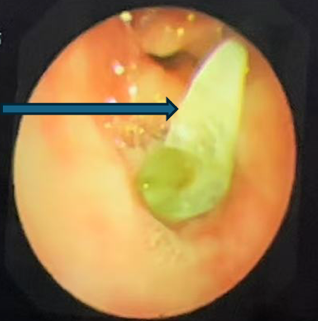

支气管镜下的景象触目惊心:乐乐右主支气管管腔内满是脓性分泌物,且增生的肉芽组织堵塞了右上叶支气管开口。在更深处,一个看似尖锐异物死死堵住了右中间支气管管腔。

支气管镜检查显示右上叶支气管肉芽增生,完全堵塞开口

支气管镜检查显示右中间段支气管异物堵塞,镜下看似尖锐,表面大量黄绿色分泌物附着